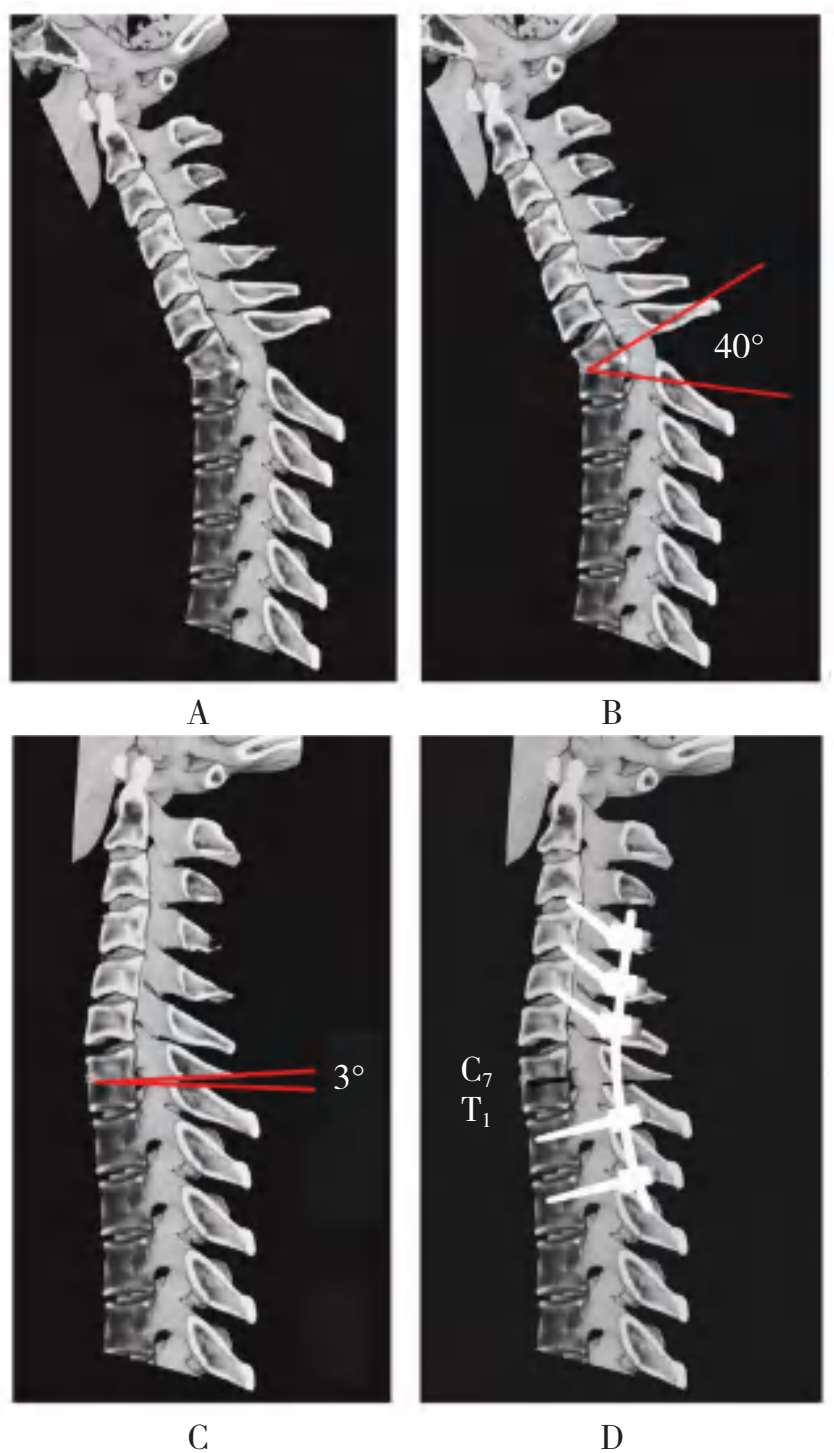

A.术前颈胸段后凸畸形47°;B.椎弓椎体次全截骨术的角度40°;C.截骨矫正闭合复位后,后凸角变为3°;D.内固定置入后,后凸角变为0°

图2-67 结核性颈胸段后凸畸形椎弓椎体次全截骨术及内固定术

A.术前颈胸段后凸畸形,椎体后缘压迫椎管;B.椎弓椎体次全截骨术的切除范围;C.截骨矫正术后,切除了椎体后缘的突出物,解除了椎管受压情况,恢复了椎管的对线;D.钉棒系统内固定后,后凸角变为0°

图2-68 结核性颈胸段后凸畸形截骨矫正术